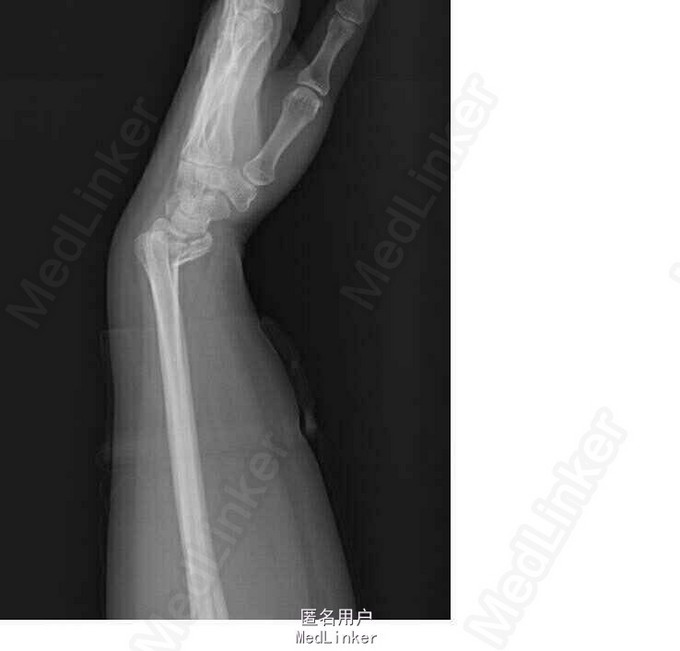

患者2小时前外伤后摔倒在地,出现左侧腕关节疼痛伴活动受限,双手掌心擦伤,左手腕部尺侧擦伤。于急诊行左手正斜位示:左侧桡骨远端骨折(barton骨折)。急诊予石膏托固定腕关节,为行手术治疗,急诊收入院

左手腕关节压痛明显,未触及骨折断端,局部软组织挫伤,肿胀明显,左手手指活动可,感觉无明显异常。 左手正斜位示:左侧桡骨远端骨折(barton骨折)

诊断:右侧桡骨远端骨折(barton骨折) 双手皮肤软组织挫伤 行左桡骨远端骨折切开复位内固定术